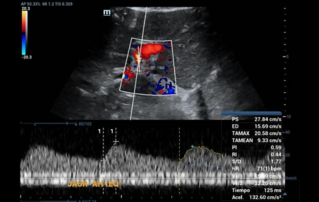

Comprehensive overview of granulosa theca cell tumors of the ovary, covering epidemiology, clinical presentation, diagnosis, treatment options, and prognosis for both adult and juvenile types.